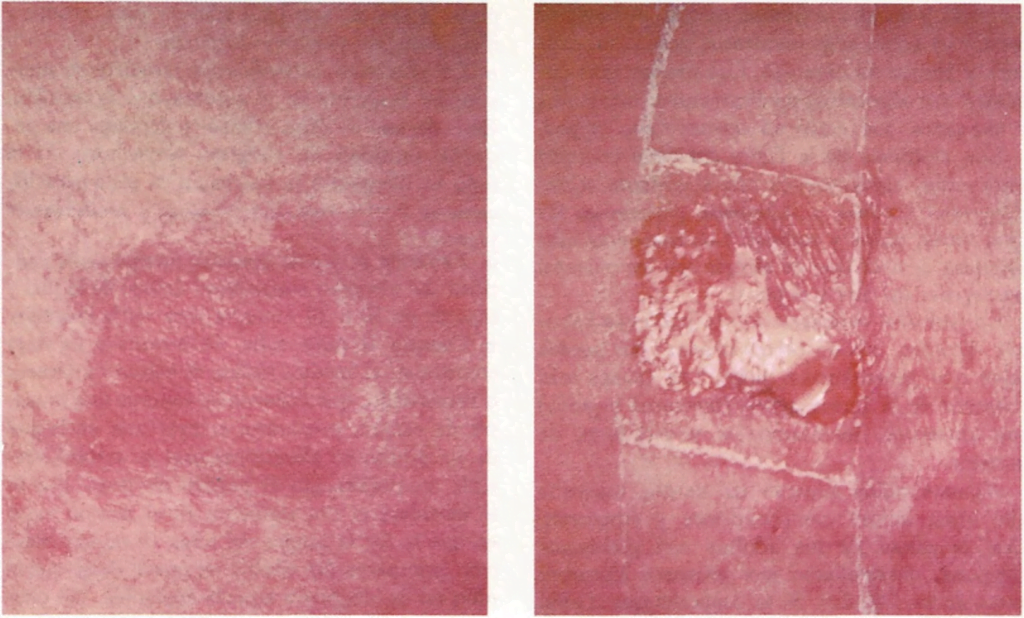

■ La prueba de escarificación consiste en unos simples rasguños en el antebrazo o la espalda. En cada uno de ellos, el médico deposita una pequeña cantidad de alérgeno sospechoso. Si el niño es alérgico a la sustancia, la zona escarificada se vuelve roja, hinchándose y produciendo picor.

■ También se puede inyectar una pequeña cantidad del alérgeno sospechoso debajo de la piel y esperar de 10 a 20 minutos para ver la reacción.

■ En la prueba del parche, el médico coloca los probables alérgenos en la piel sana y la cubre, generalmente durante 48 horas, determinando así qué sustancias pueden producir una reacción por contacto.